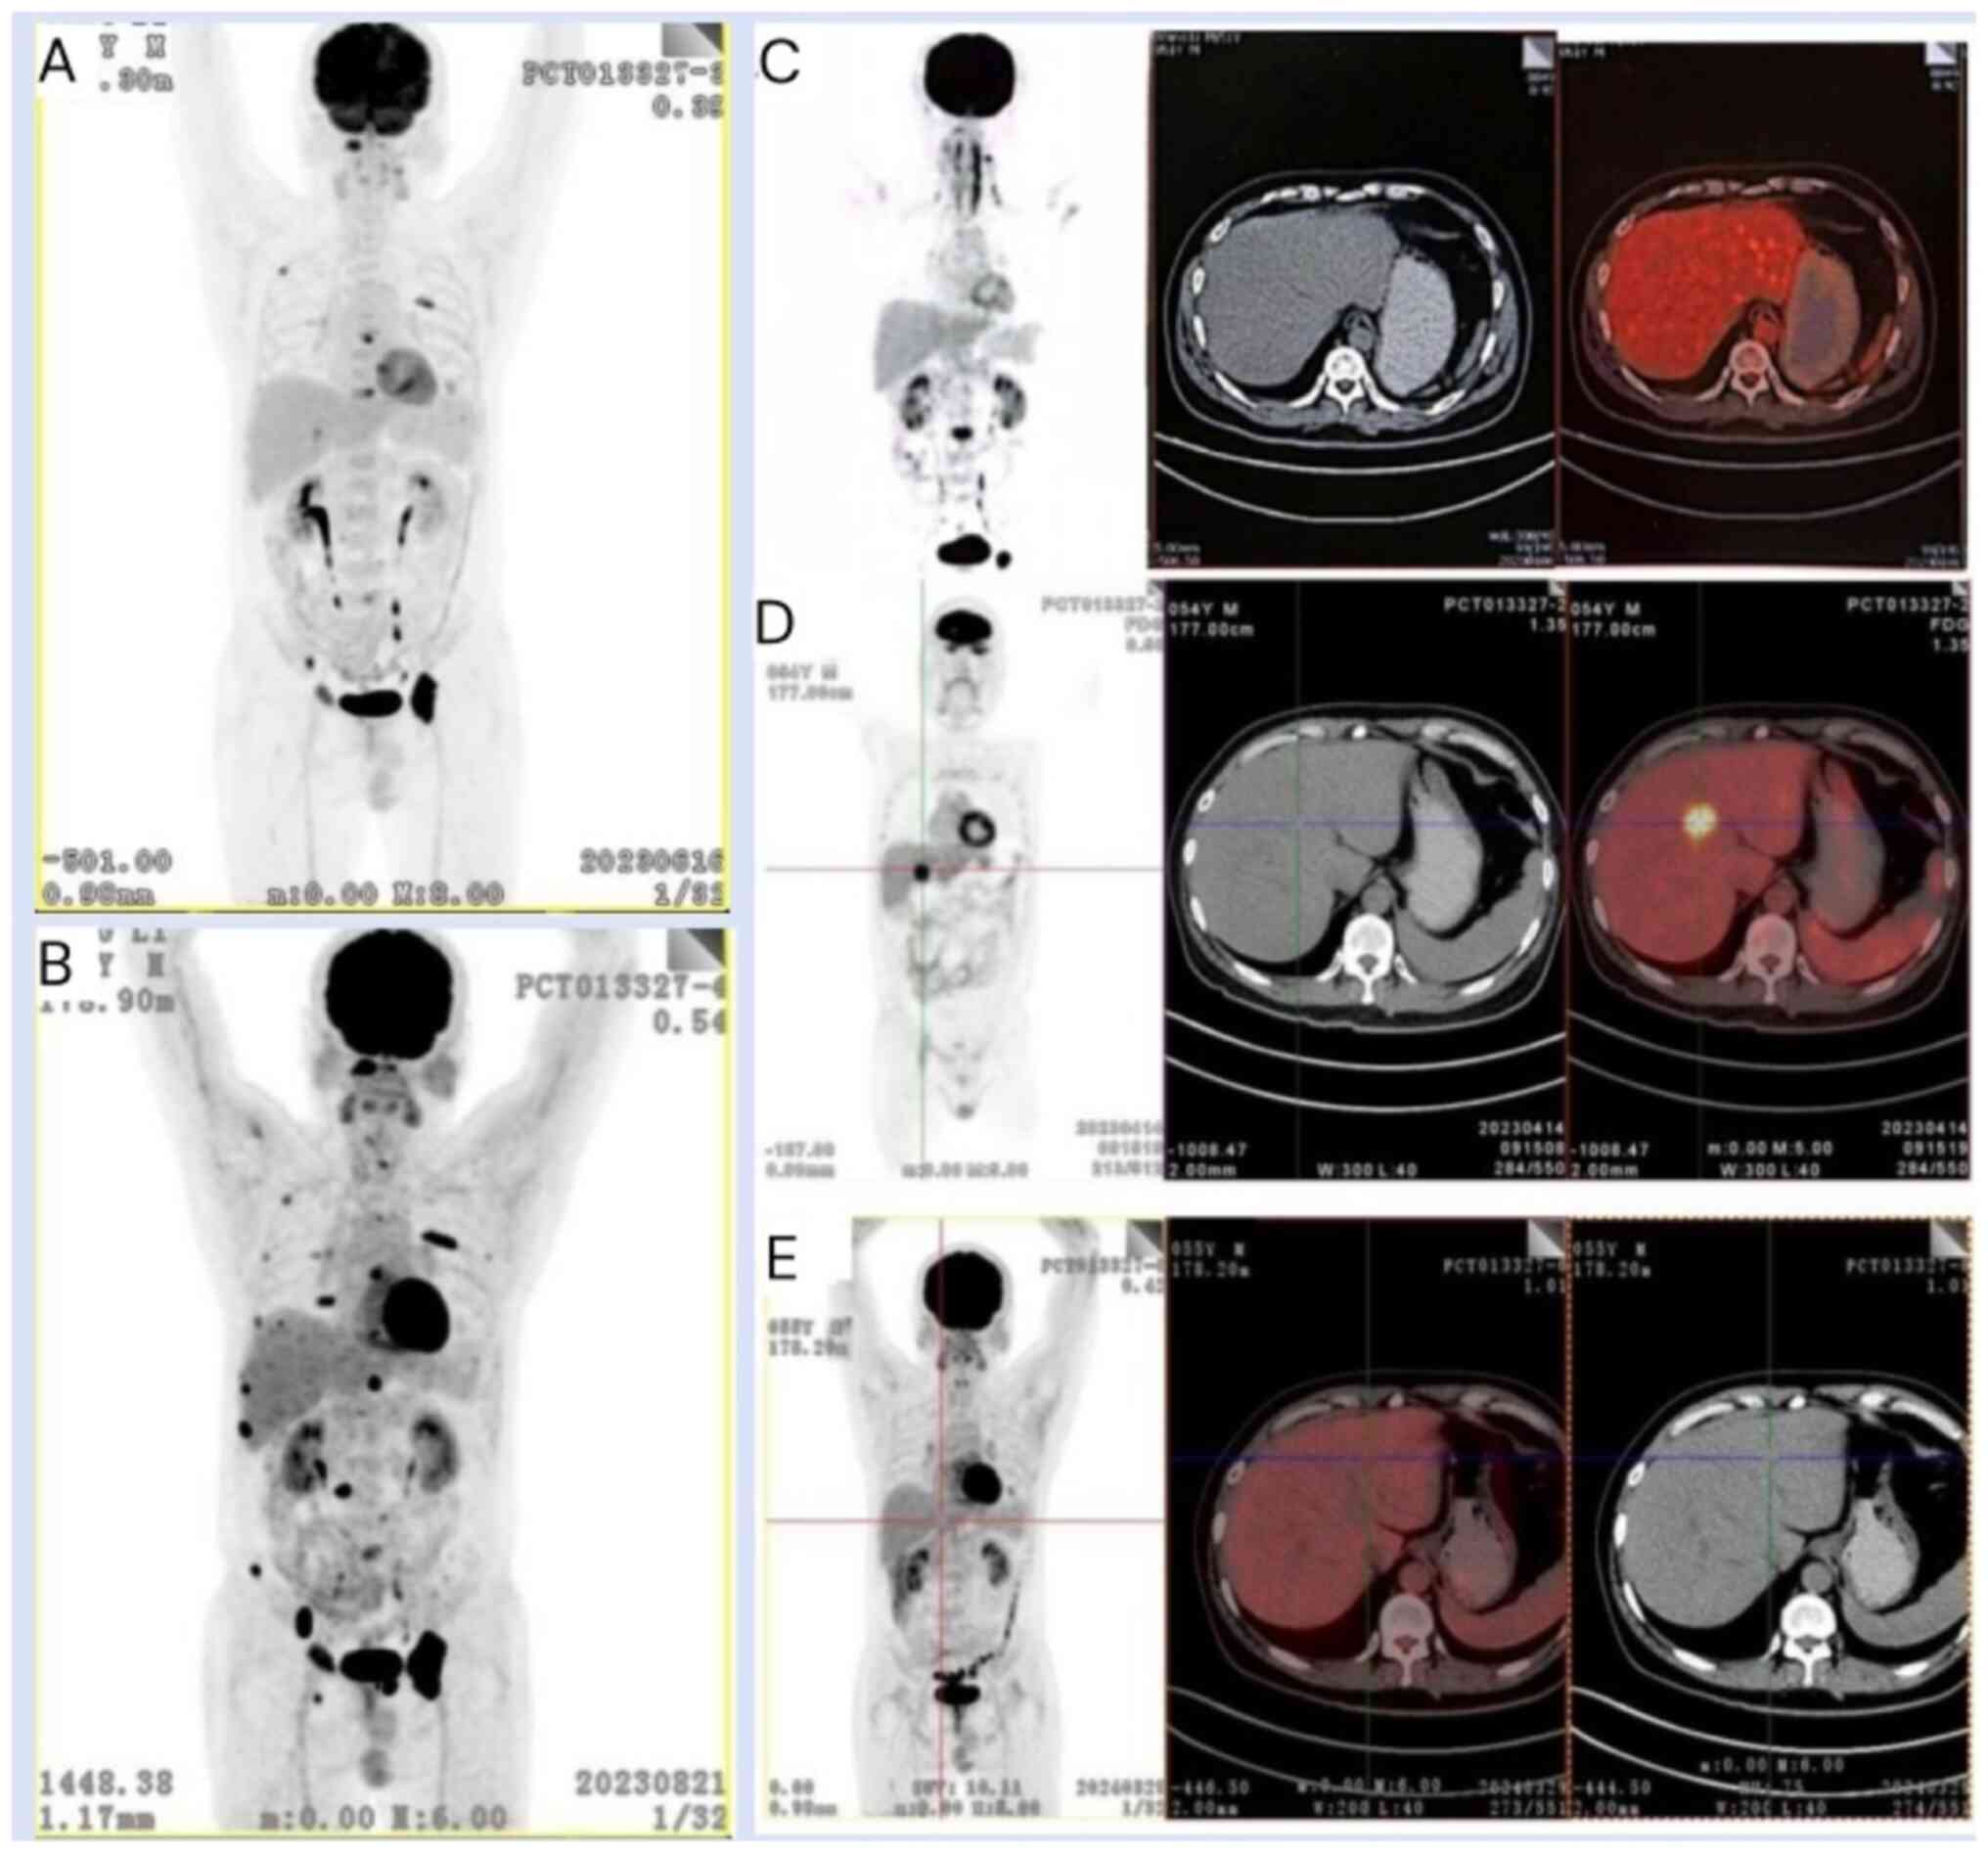

In April 2023, a whole-body PET/CT scan revealed multiple novel osteolytic bone lesions, including a newly developed lesion of hypermetabolism in segment S4 of the liver measuring ~25×24 mm compared with the previous results (Fig. 2C and D). The patient declined to undergo percutaneous biopsy of the lesion. Based on these findings, the patient was considered to have an aggressive relapse of MM with concomitant extramedullary involvement in the liver. Between April 2023 and July 2023, the patient underwent four cycles of a Dara + SKd regimen (daratumumab, 16 mg/kg, once a week for the first 8 weeks, once every 2 weeks from the 9th week; carfilzomib, 51 mg on days 1–2, 8–9 and 15–16; and dexamethasone, 10 mg on days 1–2, 8–9 and 15–16, 4 weeks as a treatment cycle) as the therapeutic protocol. Re-evaluation of the results after completing two cycles of the treatment regimen revealed the presence of an IgA-κ type M protein on immunofixation electrophoresis, accompanied by a serum IgA level of 5.84 g/l. The disease status of the patient was therefore considered to be a partial response (PR).

Whole-body PET/CT scans. (A)

Osteolytic bone destruction lesions (June 2023). (B) Osteolytic

bone destruction lesions increased (August 2023); (C) No lesion

change in the S4 segment of the liver on diagnosis (December 2019);

(D) Lesion changes in the S4 segment of the liver (April 2023). (E)

Lesion changes in the S4 segment of the liver reduced with no

hypermetabolism (March 2024). PET/CT, positron emission

tomography/computed tomography.

Figure 2.

Whole-body PET/CT scans. (A) Osteolytic bone destruction lesions (June 2023). (B) Osteolytic bone destruction lesions increased (August 2023); (C) No lesion change in the S4 segment of the liver on diagnosis (December 2019); (D) Lesion changes in the S4 segment of the liver (April 2023). (E) Lesion changes in the S4 segment of the liver reduced with no hypermetabolism (March 2024). PET/CT, positron emission tomography/computed tomography.

In July 2023, after having completed four cycles of the Dara + SKd regimen, a PET/CT scan revealed an increase in osteolytic bone destruction lesions (Fig. 2A and B). Additionally, a significant increase in the patient's serum IgA concentration to 8.27 g/l was observed, with a slight reduction in the size of the lesion located in hepatic segment S4, now measuring ~17×10 mm. Bone marrow cytological analysis indicated that plasma cells comprised ~1.5% of the total cells, and FCM analysis detected a population of 0.1% monoclonal plasma cells with an aberrant immunophenotype. The patient was considered to have progressive disease. At this point, the doctor again recommended that the patient undergo an ASCT, and the patient continued to refuse. In addition, at this time, the first Chinese anti-BCMA CAR-T cell product (FUCASO®; also known as ‘Equecabtagene Autoleucel’; IASO BioTherapeutics, Ltd. and Innovent Biologics, Inc.) was approved by the China National Medical Products Administration (NMPA). After discussion with the care team, the patient selected the anti-BCMA CAR-T cell therapy.

Follow-up examinations at 2 and 3 months following CAR-T cell infusion revealed further decreases in the patient's CAR-T cell/CD3+ T cell ratio, which decreased to 0.73 and 0.69%, respectively, and decreases in the CAR-T cell concentration to 30.71 and 19.31 cells/µl, respectively, were also observed. The patient subsequently received sintilimab (200 mg), which is a PD-1 blocker, once a month to enhance CAR-T cell function from December 2023 (4 months following CAR-T cell infusion) onwards. Subsequently, 5 months following CAR-T cell infusion, both the CAR-T cell/CD3+ T-cell ratio and the concentration of CAR-T cells dropped to 0.25% and 4.44 cells/µl, respectively. The 6-month follow-up data indicated that the percentage ratio of CAR-T cells/CD3+ T cells and the concentration of CAR-T cells increased to 0.51% and 7.85 cells/µl, respectively, before gradually decreasing up to the 10th month (Fig. 3B and C). The decay rate of CAR-T cells was decreasing. The lesion located in the S4 liver segment also showed a significant reduction to ~3×4 mm, and no hypermetabolism was observed in the PET/CT scan results at 7 months following reinfusion (scan taken in March 2024) (Fig. 2E). In addition, bone marrow biopsy confirmed the absence of clonal plasma cells, and the patient was classified as having achieved sCR.